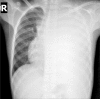

A pleural effusion is an excessive accumulation of fluid in the pleural space. It can pose a diagnostic dilemma to the treating physician because it may be related to disorders of the lung or pleura, or to a systemic disorder. Patients most commonly present with dyspnea, initially on exertion, predominantly dry cough, and pleuritic chest pain. To treat pleural effusion appropriately, it is important to determine its etiology. However, the etiology of pleural effusion remains unclear in nearly 20% of cases. Thoracocentesis should be performed for new and unexplained pleural effusions. Laboratory testing helps to distinguish pleural fluid transudate from an exudate. The diagnostic evaluation of pleural effusion includes chemical and microbiological studies, as well as cytological analysis, which can provide further information about the etiology of the disease process. Immunohistochemistry provides increased diagnostic accuracy. Transudative effusions are usually managed by treating the underlying medical disorder. However, a large, refractory pleural effusion, whether a transudate or exudate, must be drained to provide symptomatic relief. Management of exudative effusion depends on the underlying etiology of the effusion. Malignant effusions are usually drained to palliate symptoms and may require pleurodesis to prevent recurrence. Pleural biopsy is recommended for evaluation and exclusion of various etiologies, such as tuberculosis or malignant disease. Percutaneous closed pleural biopsy is easiest to perform, the least expensive, with minimal complications, and should be used routinely. Empyemas need to be treated with appropriate antibiotics and intercostal drainage. Surgery may be needed in selected cases where drainage procedure fails to produce improvement or to restore lung function and for closure of bronchopleural fistula.